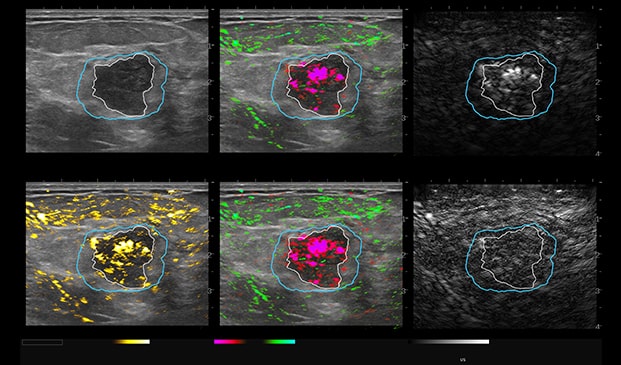

Case Example 5:

59-year-old female presents with a new mammographic asymmetry on the left breast.

A 1.2 cm mass is seen on ultrasound with some doppler signal along periphery of mass.

Case Example 5: Observations

With OA imaging we can see negative internal findings but positive external features in the boundary and peripheral zones.

We can see feeding and draining vessels or “whiskers” in the boundary and peripheral zones on OA.

Radiating vessels continue from the peripheral zone into the boundary zone and count as features in both zones.

Invasive Ductal Carcinoma Grade I

- ER+

- HER2-

- PR-

- Ki67=10%

The mass was up-classified to BI-RADS 5. Unlike TNC, luminal A masses typically present with external features in the boundary and peripheral zones and no OA internal features. Typically, luminal A masses have a low Ki67 and tend to have less internal angiogenesis and deoxygenation.